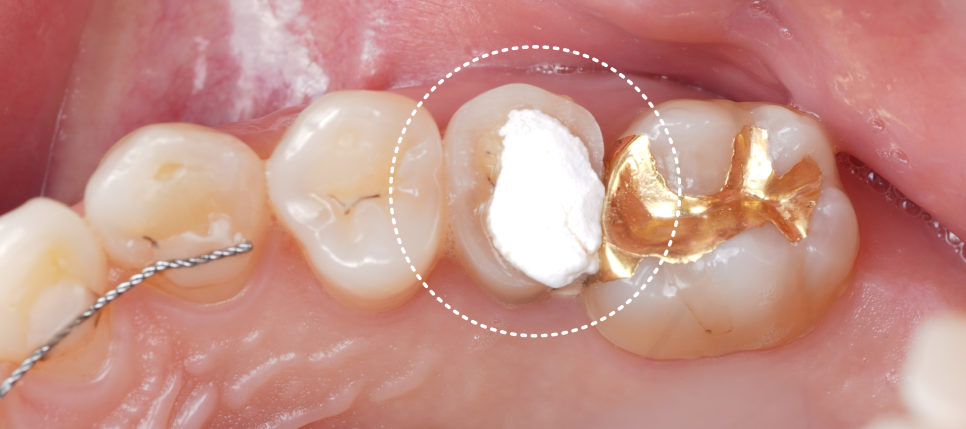

내원하셔서 확인해 보니 오른쪽 위 작은 어금니는 이미 신경치료가 끝난 상태였고 안은 임시 재료로 막혀 있었습니다.

촬영일 : 251124

“신경치료를 해서 망했다”가 아니라 “이제 어떻게 마무리할 것이냐”가 관건이었는데요.

교합면(씹는 면)은 이미 어느 정도 삭제가 되어 있었지만 나머지는 어느 정도 남아 있는 상태더라고요.